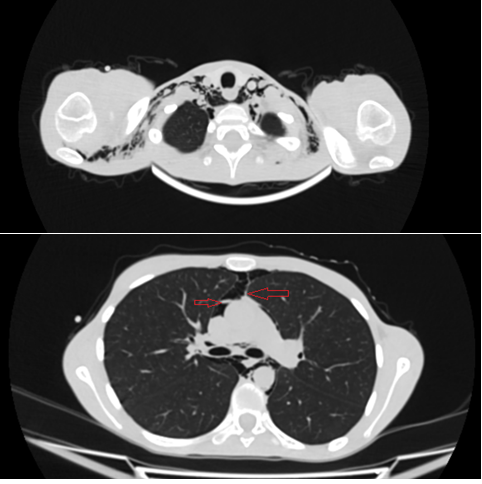

Presentamos el caso de una adolescente de sexo femenino quien cumple criterios clínicos de anorexia nerviosa y presenta dolor torácico, documentándose pneumomediastino espontáneo (PE). El PE se define como presencia de gas libre en el mediastino en ausencia de causa precipitante.

Clínicamente, el síntoma principal es el dolor torácico, seguido de disnea y a la exploración física es importante reconocer signos específicos, de los cuales el más frecuente es el enfisema subcutáneo, así como el signo de Hamman considerado patognomónico.